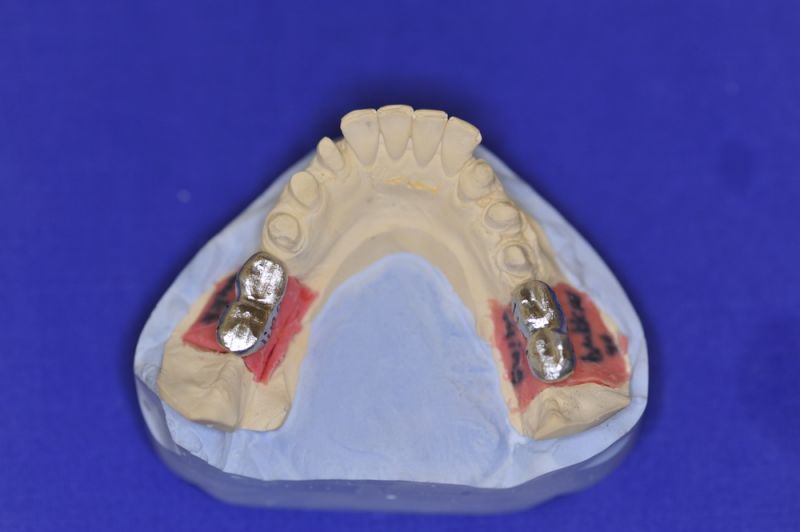

Neuromuskulär zentrierte Bisslage. Gerüste werden unbelastet durch das "Zahnfleisch" nach oben gehoben

Nun stellte sich heraus, dass der Abstand zwischen den Implantaten sehr gering war, weil die Einschubrichtungen der Aufbauten sich zum Teil gegenseitig im Wege standen. Konfektionierte Teile mussten individuell umgeschliffen werden, dabei das Ziel, den Biss korrekt einzustellen nicht aus dem Auge zu verlieren.

Heute war nun Gerüsteinprobe, mit all den Problemen der Umsetzung zwischen Laborsituation und Mundsituation. Siehe Stichpunkt "Schnittstellenproblematik"! was bei Zähnen, auf Grund deren Eigenbeweglichkeit im Kieferkochen kein Problem wäre, ist bei drei unbeweglichen Implantaten ein Riesenproblem. Darüber spricht nur in aller Regel Niemand! Es musste viel fein nachgearbeitet werden.